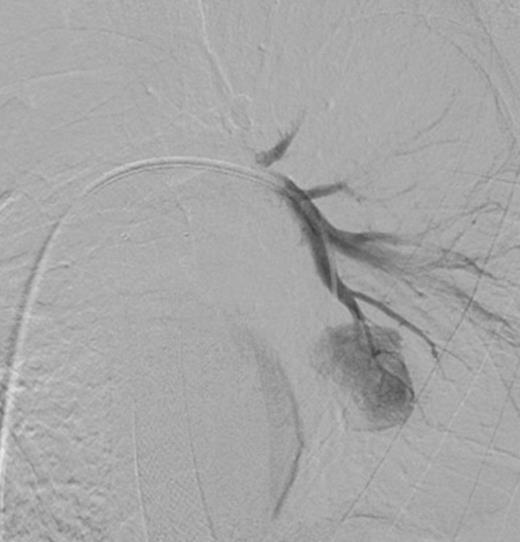

Selective digital subtraction angiography image of left lower lobe pulmonary artery, demonstrating filling of the inflammatory aneurysm and depicting the feeding branches clearly

Digital subtraction angiography post deployment of the AVP 4 device in the PA branch feeding the aneurysm (arrow). No residual or collateral filling seen